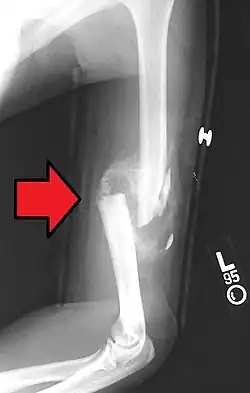

Distal humerus fractures usually occur as a result of physical trauma to the elbow region. If the elbow is bent during the trauma, then the olecranon is driven upward, producing a T- or Y-shaped fracture or displacing one of the condyles.[7]

A displaced supracondylar fracture in a child

Fractures of the humerus are classified based on the location of the fracture and then by the type of fracture. There are three locations that humerus fractures occur: at the proximal location, which is the top of the humerus near the shoulder, in the middle, which is at the shaft of the humerus, and the distal location, which is the bottom of the humerus near the elbow.[9] Proximal fractures are classified into one of four types of fractures based on the displacement of the greater tubercle, the lesser tubercle, the surgical neck, and the anatomical neck, which are the four parts of the proximal humerus, with fracture displacement being defined as at least one centimeter of separation or an angulation greater than 45 degrees. One-part fractures involve no displacement of any parts of the humerus, two-part fractures have one part displaced relative to the other three; three-part fractures have two displaced fragments, and four-part fractures have all fragments displaced from each other.[13][14][3] Fractures of the humerus shaft are subdivided into transverse fractures, spiral fractures, "butterfly" fractures, which are a combination of transverse and spiral fractures, and pathological fractures, which are fractures caused by medical conditions.[12] Distal fractures are split between supracondylar fractures, which are transverse fractures above the two condyles at the bottom of the humerus, and intercondylar fractures, which involve a T- or Y-shaped fracture that splits the condyles.[7]